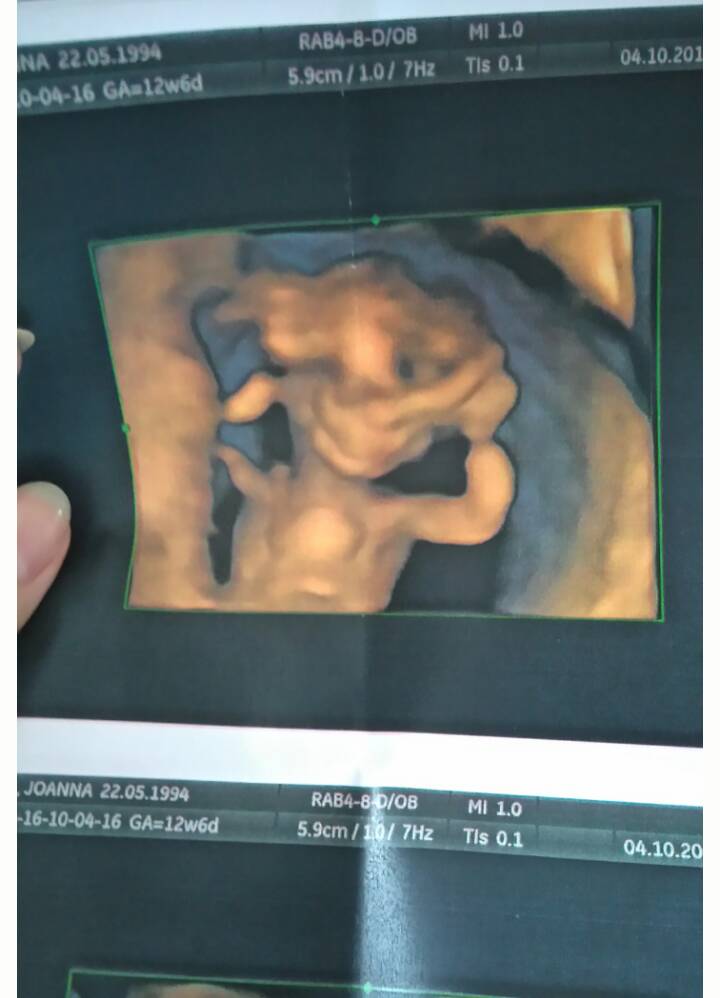

A ja nic nie widzę